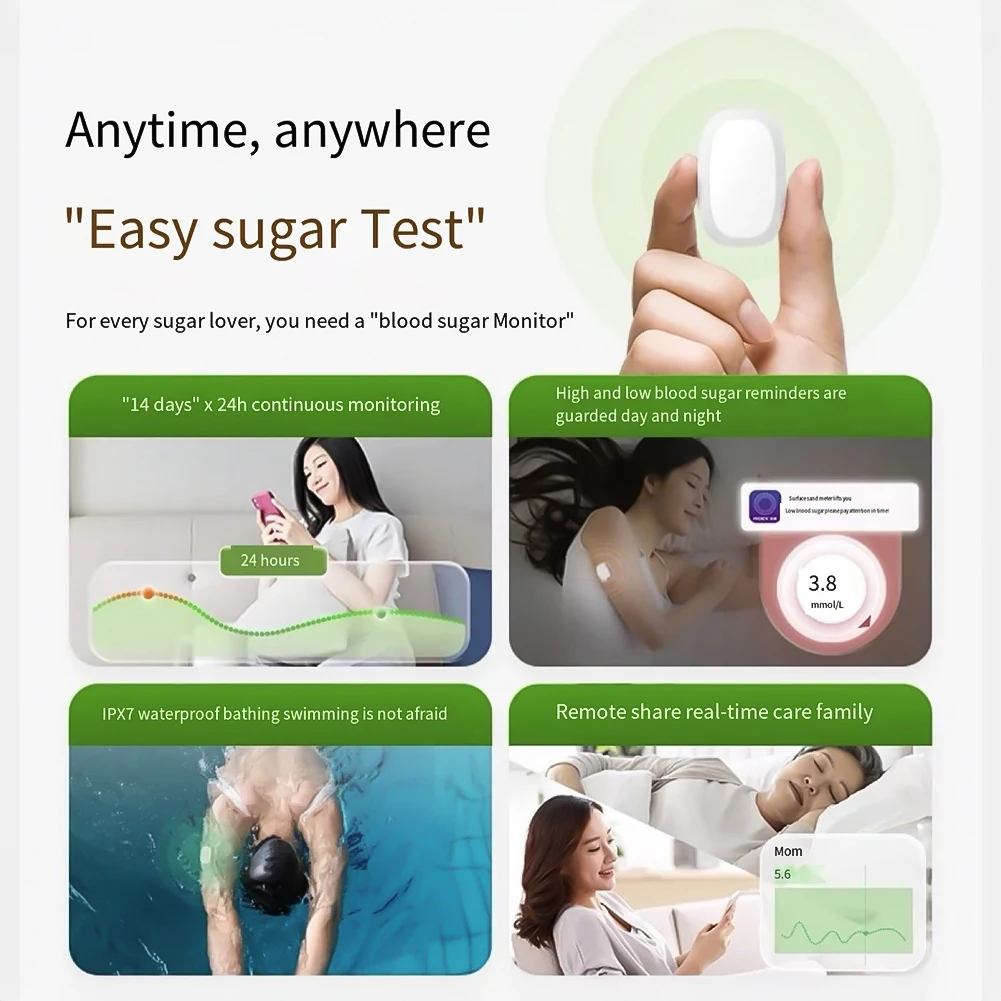

Battery Included: Yes

Brand Name: NoEnName_Null

Certification: CE

Choice: yes

Display Type: DIGITAL

Hign-concerned Chemical: None

Origin: Mainland China

semi_Choice: yes